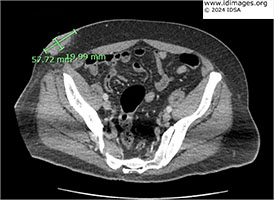

A computed tomography (CT) scan of the abdomen showed a 4.8 x 2.0 cm soft tissue mass in the right lower abdominal subcutaneous fat abutting the skin (Figure 2). In addition, a 2.5 cm soft tissue nodule anterior to the inferior left rectus abdominis muscle and an ill-defined 3.8 x 1.1 cm soft tissue thickening/stranding anterior to the inferior right rectus abdominis muscle were seen. A 2.3 cm soft tissue nodule in the prepubic subcutaneous fat was also identified.

- Figure 2: CT abdomen showed a 4.8 x 2.0 cm soft tissue mass in the right lower abdominal subcutaneous fat abutting the skin.